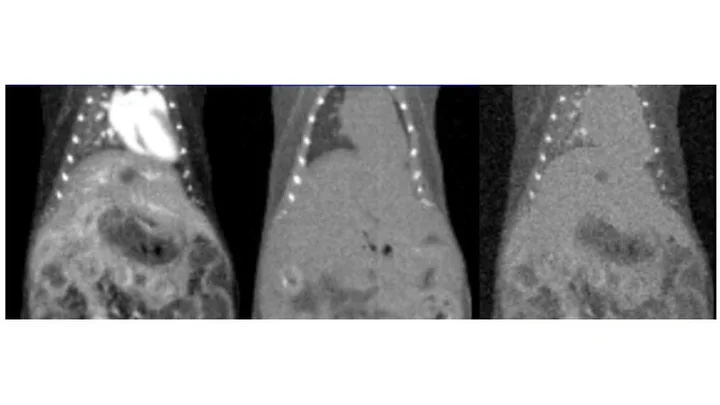

Breadcrumb Home Applications Gallery Gallery Applications Videos Gallery Library of Recent Studies Cancer Biology Coupling IL-2 with IL-10 to mitigate toxicity and enhance antitumor immunity. Ahn et al. 2025. Cell Rep Med. PGC-1α drives small cell neuroendocrine cancer progression toward an ASCL1-expressing subtype with increased mitochondrial capacity. Varuzhanyan et al. 2024. Proc Natl Acad Sci U S A. 89Zr-ImmunoPET for the Specific Detection of EMP2-Positive Tumors. Chan et al. 2024. Mol Cancer Ther. 18F-Labeled brain-penetrant EGFR tyrosine kinase inhibitors for PET imaging of glioblastoma. Narayanam et al. 2023. Chem Sci. M2 isoform of pyruvate kinase rewires glucose metabolism during radiation therapy to promote an antioxidant response and glioblastoma radioresistance. Bailleul et al. 2023. Neuro Oncol. Spatial mapping of mitochondrial networks and bioenergetics in lung cancer. Han et al. 2023. Nature. Anti-PD-1/L1 lead-in before MAPK inhibitor combination maximizes antitumor immunity and efficacy. Wang et al. 2021. Cancer Cell. In vivo imaging of mitochondrial membrane potential in non-small-cell lung cancer. Momcilovic et al. 2019. Nature. Immunotherapy Low-dose exposure to PBDE disrupts genomic integrity and innate immunity in mammary tissue. Lamkin et al. 2022. Front Genet. Immuno-PET in Inflammatory Bowel Disease: Imaging CD4-Positive T Cells in a Murine Model of Colitis. Freise et al. 2018. J Nucl Med. ImmunoPET of Malignant and Normal B Cells with 89Zr- and 124I-Labeled Obinutuzumab Antibody Fragments Reveals Differential CD20 Internalization In Vivo. Zettlitz et al. 2017. Clin Cancer Res. Detection of immune responses after immunotherapy in glioblastoma using PET and MRI. Antonios et al. 2017. Proc Natl Acad Sci U S A. Neuroscience [18F]FDG-PET and [18F]MPPF-PET are brain biomarkers for the creatine transporter Slc6a8 loss of function mutation. Day et al. 2025. Sci Rep. Gene therapy for guanidinoacetate methyltransferase deficiency restores cerebral and myocardial creatine while resolving behavioral abnormalities. Khoja et al. 2022. Mol Ther Methods Clin Dev. Regional distribution of SGLT activity in rat brain in vivo. Yu et al. 2013. Am J Physiol Cell Physiol. [F-18]FDDNP microPET imaging correlates with brain Aβ burden in a transgenic rat model of Alzheimer disease: effects of aging, in vivo blockade, and anti-Aβ antibody treatment. Teng et al. 2011. Neurobiol Dis. Cardiology Preclinical evaluation of high-resolution CT, 18F-FDG, and 18F-NaF PET imaging for longitudinal monitoring of atherosclerosis. Tamboline et al. 2025. Eur J Nucl Med Mol Imaging. A humanized monoclonal antibody targeting an ectonucleotidase rescues cardiac metabolism and heart function after myocardial infarction. Li et al. 2024. Cell Rep Med. Invasive electrochemical impedance spectroscopy with phase delay for experimental atherosclerosis phenotyping. Chen et al. 2024. FASEB J. Changes in microarchitecture of atherosclerotic calcification assessed by 18F-NaF PET and CT after a progressive exercise regimen in hyperlipidemic mice. Hsu et al. 2021. J Nucl Cardiol. Statin Effects on Vascular Calcification: Microarchitectural Changes in Aortic Calcium Deposits in Aged Hyperlipidemic Mice. Xian et al. 2021. Arterioscler Thromb Vasc Biol. Statin Effects on Vascular Calcification: Microarchitectural Changes in Aortic Calcium Deposits in Aged Hyperlipidemic Mice. Xian et al. 2021. Arterioscler Thromb Vasc Biol. Effects of teriparatide on morphology of aortic calcification in aged hyperlipidemic mice. Hsu et al. 2018. Am J Physiol Heart Circ Physiol. Metabolism PPARγ-dependent remodeling of translational machinery in adipose progenitors is impaired in obesity. Siqueira et al. 2024. Cell Rep. Dietary control of peripheral adipose storage capacity through membrane lipid remodelling. Tol et al. 2025. Nat Metab. Drug Development Recent developments in translational imaging of in vivo gene therapy outcomes. Day et al. 2025. Mol Ther. A Glucose-Responsive Glucagon-Micelle for the Prevention of Hypoglycemia. Vinciguerra et al. 2024. ACS Cent Sci. A humanized monoclonal antibody targeting an ectonucleotidase rescues cardiac metabolism and heart function after myocardial infarction. Li et al. 2024. Cell Rep Med. An HK2 Antisense Oligonucleotide Induces Synthetic Lethality in HK1-HK2+ Multiple Myeloma. Xu et al. 2019. Cancer Res. A precision therapeutic strategy for hexokinase 1-null, hexokinase 2-positive cancers. Xu et al. 2018. Cancer Metab. Development of new deoxycytidine kinase inhibitors and noninvasive in vivo evaluation using positron emission tomography. Murphy et al. 2013. J Med Chem. On-demand drug release system for in vivo cancer treatment through self-assembled magnetic nanoparticles. Lee et al. 2013. Angew Chem Int Ed Engl. Accurate Measurements by High-Resolution CT and MRI Supramolecular hydrogel actuators with reprogrammable magnetic orientation by locally mediated viscoelasticity and pinning force. Zhang et al. 2025. Sci Adv. Gene therapy for guanidinoacetate methyltransferase deficiency restores cerebral and myocardial creatine while resolving behavioral abnormalities. Khoja et al. 2022. Mol Ther Methods Clin Dev. Interactions between maternal fluoxetine exposure, the maternal gut microbiome and fetal neurodevelopment in mice. Vuong et al. 2021. Behav Brain Res. Imaging Technology Development Real-Time in Vivo Bacterial Imaging by Computed Tomography and Fluorescence Using Phage-Gold Nanorod Bioconjugates as Contrast Agents. Peng et al. 2025. ACS Biomater Sci Eng. Retrospective Cardiac Gating with A Prototype Small-Animal X-ray Computed Tomograph. Taschereau et al. 2025. J Vis Exp. Novel Quantification Protocol for Cardiovascular Calcification Progression Using Longitudinal MicroPET/MicroCT Images. Day et al. 2024. J Vis Exp. High-throughput radio-TLC analysis. Wang et al. 2021. Nucl Med Biol. Performance evaluation of HiPET, a high sensitivity and high resolution preclinical PET tomograph. Gu et al. 2020. Phys Med Biol. Prediction of major torso organs in low-contrast micro-CT images of mice using a two-stage deeply supervised fully convolutional network. Wang et al. 2019. Phys Med Biol. Performance Evaluation of G8, a High-Sensitivity Benchtop Preclinical PET/CT Tomograph. Gu et al. 2019. J Nucl Med. 3D Printing for Understanding Anatomy Three-Dimensional Magnetic Resonance Imaging of the Human Stellate Ganglion. Nakajo et al. 2025. Clin Anat. Understanding Cardiac Anatomy and Imaging to Improve Safety of Procedures: The Subclavian Artery and Vein. Sato et al. 2025. JACC Case Rep. Understanding Cardiac Anatomy and Imaging to Improve Safety of Procedures: The Femoral Artery and Vein: Part 2. Sato et al. 2024. JACC Case Rep. Pipeline for Multi-Scale Three-Dimensional Anatomic Study of the Human Heart. Hanna et al. 2024. J Vis Exp. Radiochemistry Technology Development Rapid Concentration of Ga-68 and Proof-of-Concept Microscale Labeling of [68Ga]Ga-PSMA-11 in a Droplet Reactor. Lu et al. 2024. Molecules. Scalable droplet-based radiosynthesis of [18F]fluorobenzyltriphenylphosphonium cation ([18F]FBnTP) via a "numbering up" approach. Lu et al. 2024. Lab Chip. Proof-of-concept optimization of a copper-mediated 18F-radiosynthesis of a novel MAGL PET tracer on a high-throughput microdroplet platform and its macroscale translation. Lu et al. 2023. Lab Chip. Accelerating radiochemistry development: Automated robotic platform for performing up to 64 droplet radiochemical reactions in a morning. Jones et al. 2023. Chem Eng J. Detrimental impact of aqueous mobile phases on 18F-labelled radiopharmaceutical analysis via radio-TLC. Laferriere-Holloway et al. 2023. Anal Methods. High-pressure, compact, modular radiosynthesizer for production of positron emitting biomarkers. Amaraesekera et al. 2013. Appl Radiat Isot. Simplified programming and control of automated radiosynthesizers through unit operations. Clagget et al. 2013. EJNMMI Res. High-Efficiency Production of Radiopharmaceuticals via Droplet Radiochemistry: A Review of Recent Progress. Wang et al. 2020. Mol Imaging. A simple and efficient automated microvolume radiosynthesis of [18F]Florbetaben. Lisova et al. 2020. EJNMMI Radiopharm Chem. Probe and Assay Development Comparison of the Efficacy and Sensitivity of Alternative PET Reporter Gene/PET Reporter Probe Systems That Minimize Biological Variables. Xu et al. 2020. Methods Mol Biol. A Transmetalation Reaction Enables the Synthesis of [18F]5-Fluorouracil from [18F]Fluoride for Human PET Imaging. Hoover et al. 2016. Organometallics. INDs for PET molecular imaging probes-approach by an academic institution. Mosessian et al. 2014. Mol Imaging Bio. Positron emission tomography probe demonstrates a striking concentration of ribose salvage in the liver. Clark et al. 2014. Proc Natl Acad Sci U S A. Tracer Kinetic Modeling Improved modeling of in vivo kinetics of slowly diffusing radiotracers for tumor imaging. Wilks et al. 2014. J Nucl. Med. Improved derivation of input function in dynamic mouse [18F]FDG PET using bladder radioactivity kinetics. Wong et al. 2013. Mol Imaging Biol. Influence of dietary state and insulin on myocardial, skeletal muscle and brain [F]-fluorodeoxyglucose kinetics in mice. Effects of administration route, dietary condition, and blood glucose level on kinetics and uptake of 18F-FDG in mice. Wong et al. 2011. J Nucl Med.